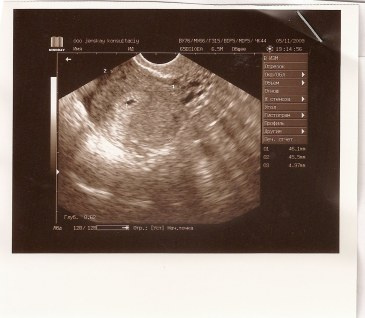

Эта ситуация одна из самых сложных в диагностическом плане . В матке обнаруживается плодное яйцо, но оно категорически не соответствует сроку, наблюдается существенное отставание роста .

Плодное яйцо образуется после слияния яйцеклетки и сперматозоида . Если оно расположено в матке, то можно говорить о маточной беременности . Если врач, который проводит ультразвуковое . . .

На 4 сутки эмбрион перемещается в полость матки, где продолжает делиться и увеличиваться в размере . На УЗИ плодное яйцо в матке можно увидеть только на 5 неделе .